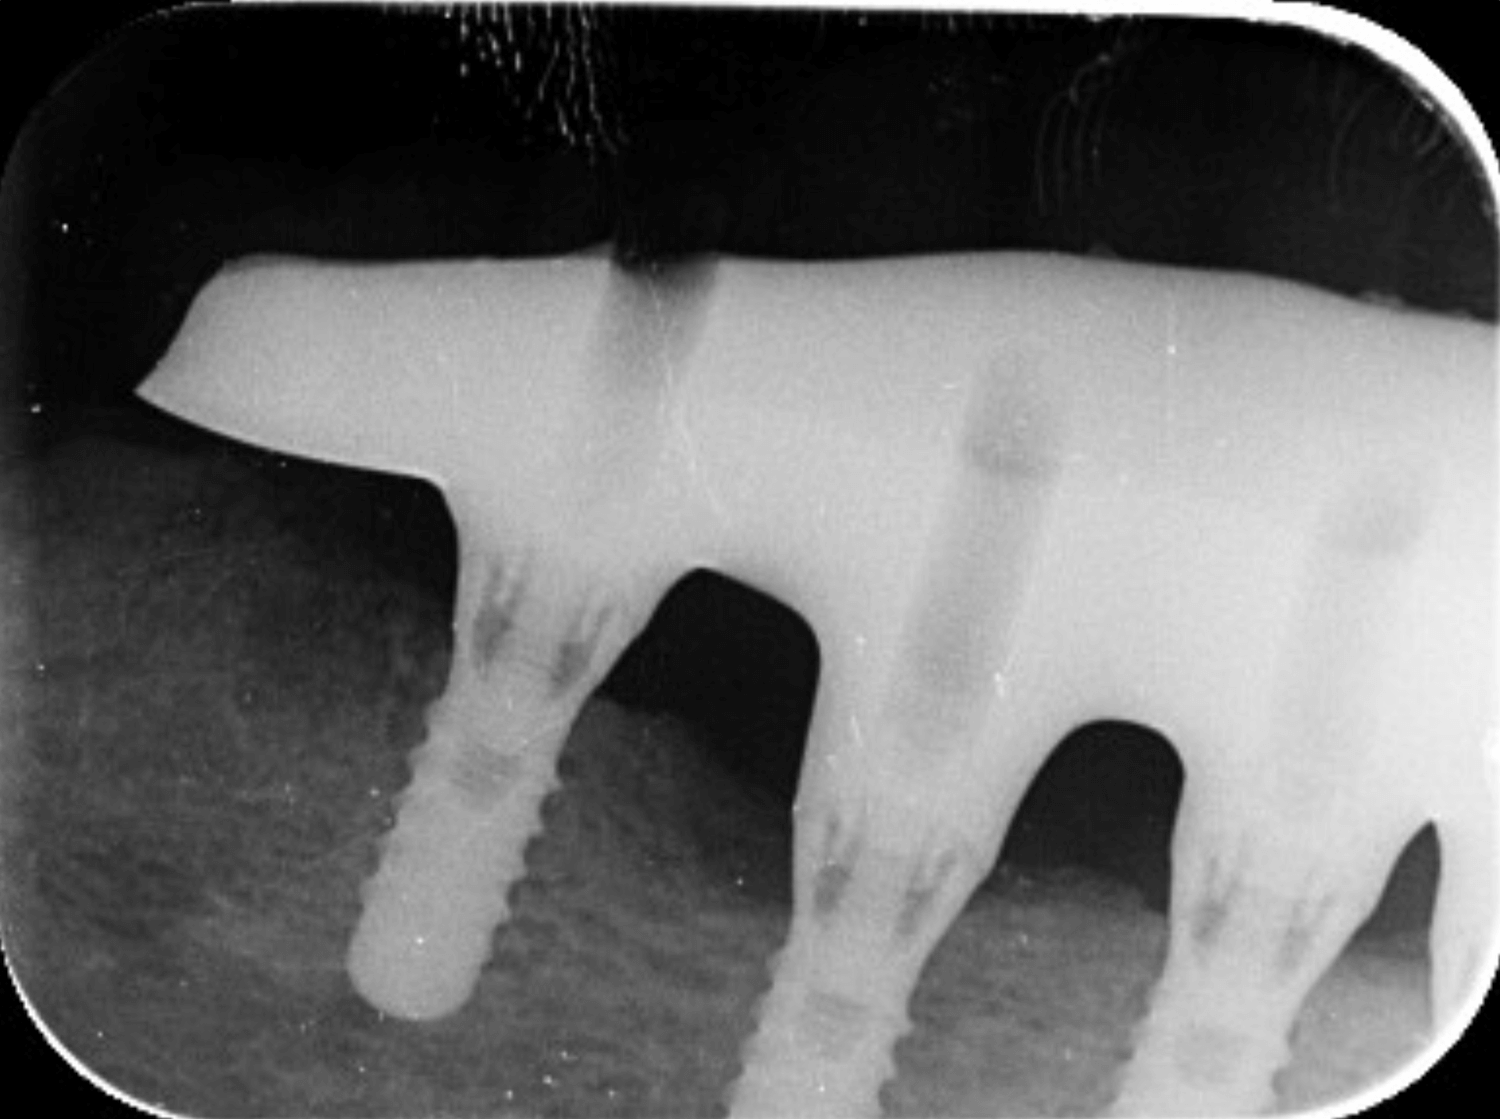

Přesnost titanové konstrukce

Kontrola pasivního dosedu

Před jakýmkoliv zásahem je nutné zkontrolovat, zda konstrukce pasivně sedí na všech implantátech.

Kontrola a úpravy pod mikroskopem

Veškeré úpravy titanové konstrukce je nutné provádět výhradně pod mikroskopem. Zajišťuje to maximální přesnost bez rizika změny geometrie dosedu nebo snížení stability konstrukce.